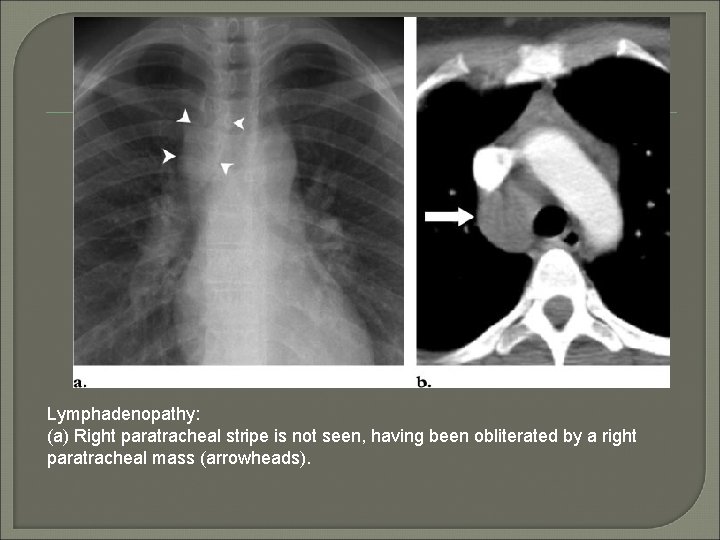

Lymphadenopathy: (a) Right paratracheal stripe is not seen, having been obliterated by a right paratracheal mass (arrowheads).